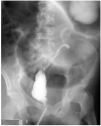

Síndrome de obstrucción intestinal